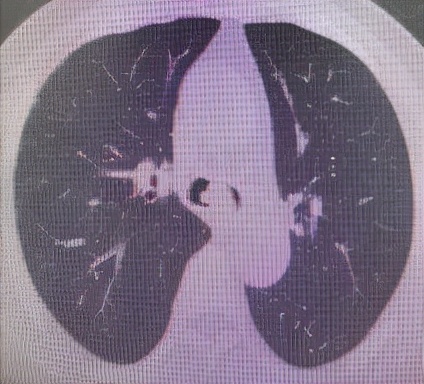

肺 部 C T (削瘤前)

于世寰主任介绍到,患者气管分叉处占位病变面积较大,已累及左、右主支气管,从肺CT影像上判断隆突区病变导致左主支气管狭窄约70-80%左右、右主支气管狭窄约50-60%左右,可操作空间十分有限,支气管镜介入治疗难度较大。隆突区占位病变已累及左右主支气管导致了呼吸困难已不适宜行外科手术治疗,必须通过支气管镜削瘤治疗来解除病人因气道梗阻导致的呼吸困难。支气管镜削瘤治疗与开胸外科手术相比,有痛苦小、创伤小、花费少、可重复性强、并发症少等优点。